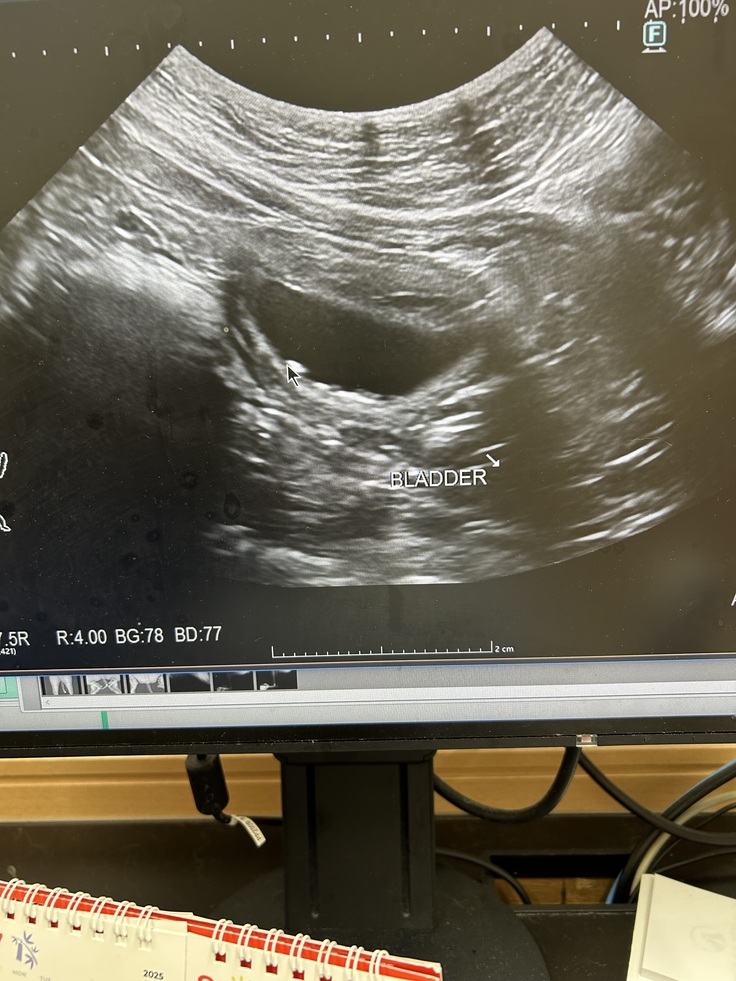

仕事から 帰宅後 なつ(女の子)が 何回もトイレに行く様子を発見。トイレ後 見ても おしっこがちゃんと出ていないので なつも急遽 病院へ。熱は 40℃ 血液検査とエコー検査。その結果 腎臓に結石が見つかりました。

結石も初めての病気なので 詳しく説明してもらいました。今の段階では 療養食と水分摂取

で様子を見るしかないそうです。今の症状が 変わらなければ 1週間後。食事も水分も取れていて おしっこがちゃんと出てくれていたら 1か月にもう一度 エコーして 結石がどうなっているか?確認するそうです。